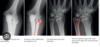

Describe this XR

Lateral XR of PIP joint V sign = dorsal widening of joint where there is minimal subluxation Fracture at volar plate/base of mid phalanx + dorsal subluxation of PIP joint